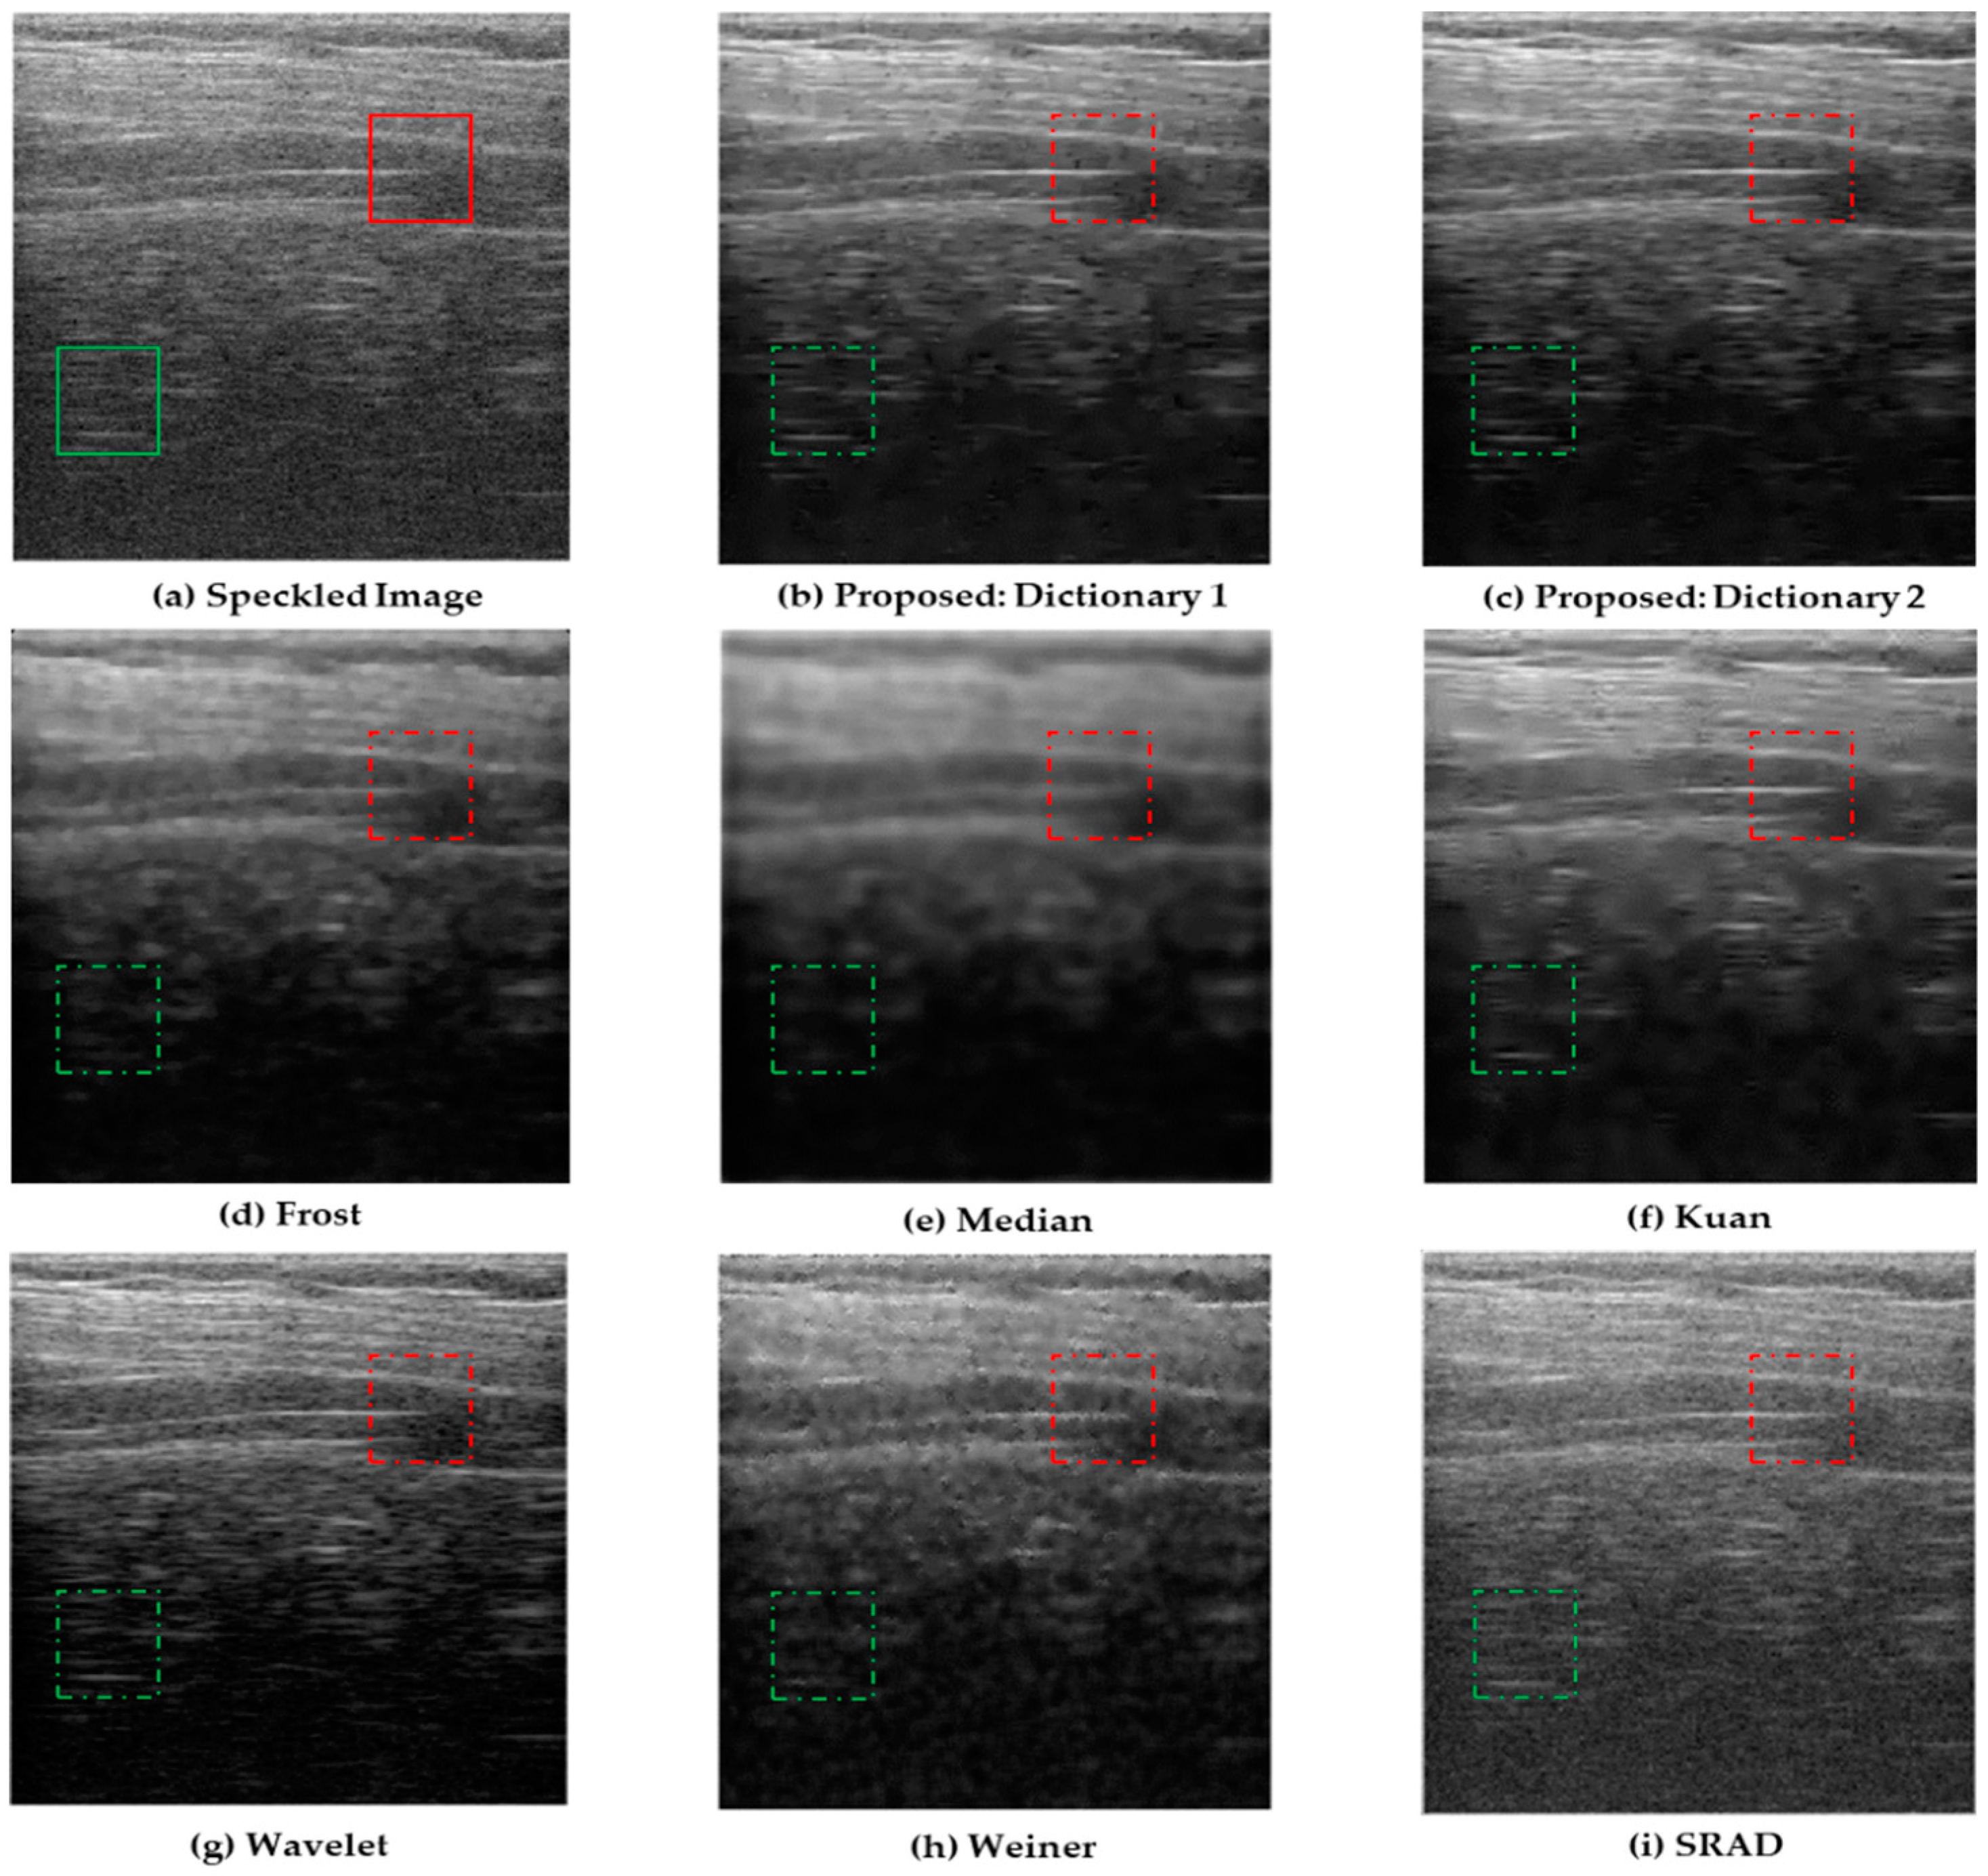

4.1. Simulations on Synthetic Images

| Noise image | 32.113 | 0.727 |

| Frost | 32.466 | 0.768 |

| Wavelet | 33.214 | 0.801 |

| Kuan | 32.895 | 0.794 |

| Median | 34.597 | 0.839 |

| SRAD | 33.434 | 0.827 |

| Weiner | 33.782 | 0.834 |

| Proposed: Dictionary 1 | 36.862 | 0.953 |

| Proposed: Dictionary 2 | 37.044 | 0.967 |